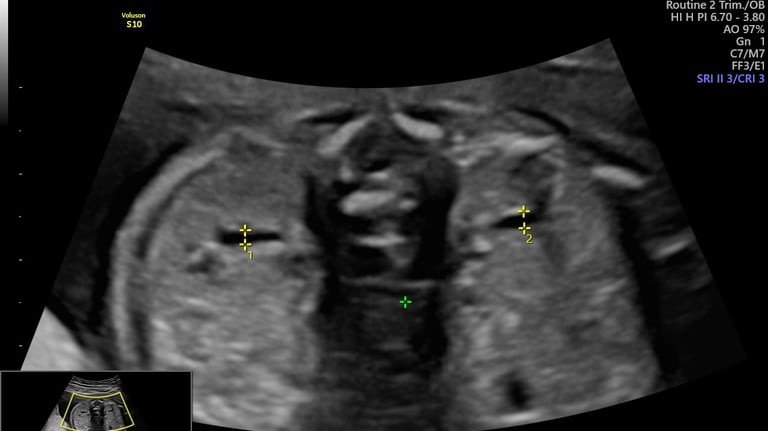

ecografía de crecimiento Doppler

24 - 40 semanas